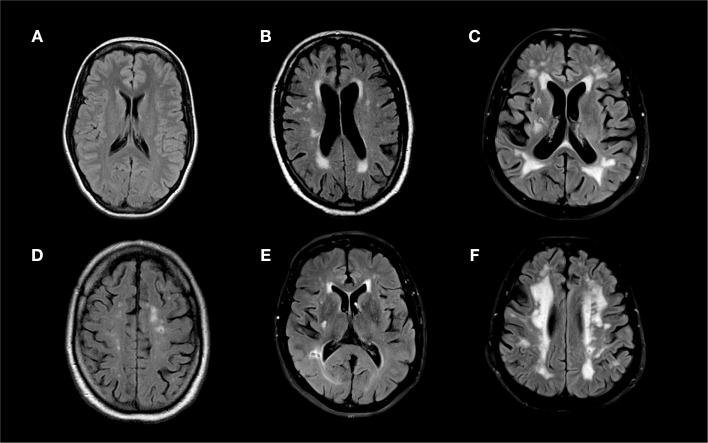

All first ischemic stroke patients who completed a novel combined oral triglyceride and glucose tolerance test and MRI between January 2009 and June 2012 were included. Fluid-attenuated inversion recovery or T2 MRI sequences were used to visualize cavitating lacunes and white matter hyperintensities, which were graded using the Wahlund visual scale.

One hundred and ninety patients were included (median age 66, IQR 52-73; 33% female; median National Institute of Health Stroke Scale 2, IQR 1-4). A forward stepwise binary logistical regression analysis applying the Hosmer-Lemeshow goodness of fit test adjusted for parameters significant in univariate analyses (at the p < 0.10 level) revealed that Wahlund scores (Wahlund 0-4: reference; Wahlund 5-10: adjusted odds ratio, 5.1; 95% confidence interval, 1.3-20.0, p = 0.019; Wahlund>10: adjusted odds ratio 9.6; 95% CI, 1.55-59.35; p = 0.015) and the highest quartile of post-challenge triglycerides (>295 mg/dL; adjusted odds ratio, 7.36; 95% confidence interval 1.24-43.70; p = 0.028) independently associated with the presence of cavitating lacunes.